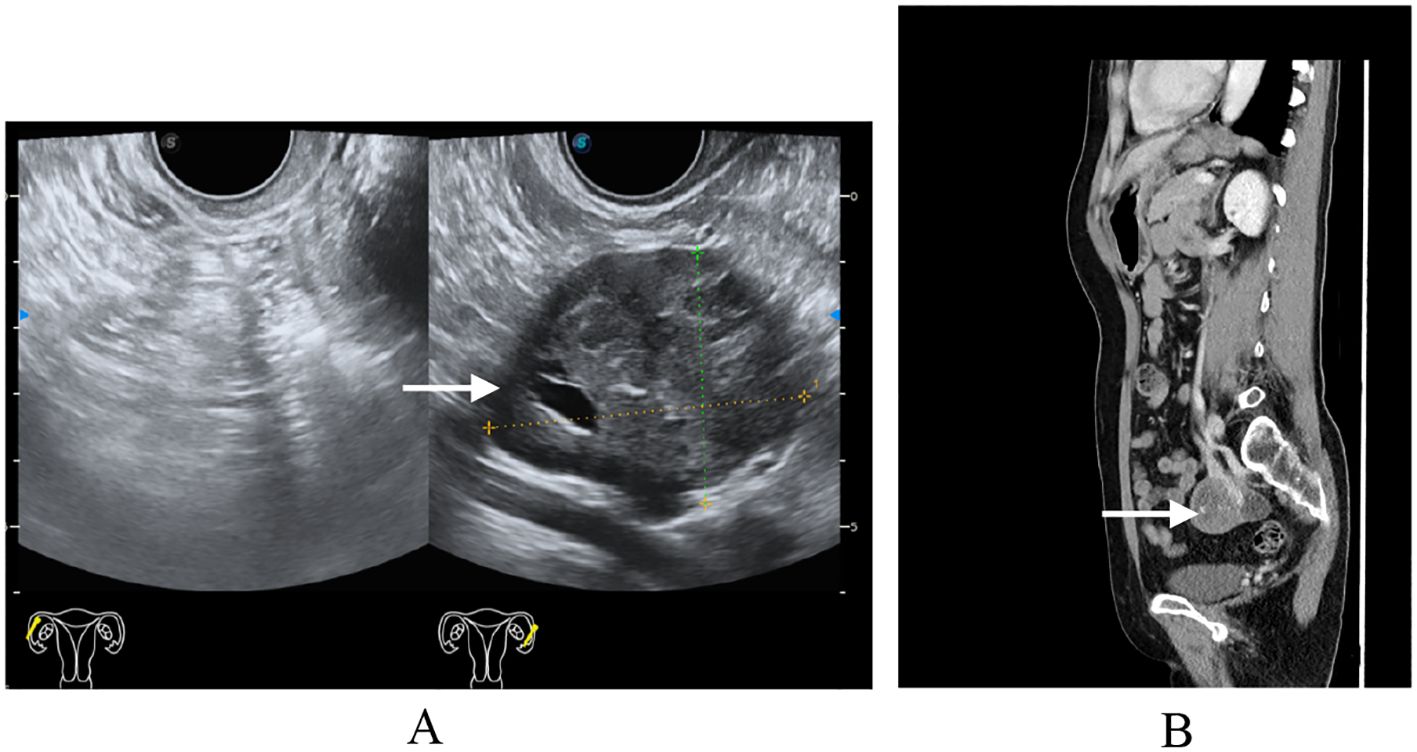

A 54-year-old postmenopausal woman, gravida 3 para 1 (G3P1) with a history of one full-term vaginal delivery and two remote-induced abortions (over 20 years ago), was admitted to our hospital following a routine physical examination in June 2024. She had no significant medical or surgical comorbidities. The patient was asymptomatic, with no abdominal discomfort, abnormal vaginal bleeding, or urinary or gastrointestinal symptoms. Her previous menstrual history was unremarkable. A comprehensive gynecological examination was conducted. Speculum examination revealed no vaginal wall lesions and a normal-appearing cervix (cervical cytology was obtained, with the results within normal limits). Bimanual examination palpated a well-defined, mobile, non-tender, approximately 5-cm mass in the left adnexa. Transvaginal ultrasonography confirmed a corresponding 5.2-cm solid left adnexal mass, demonstrating well-demarcated but irregular margins, heterogeneous echogenicity, and punctate vascular signals on color Doppler. To further characterize the lesion, contrast-enhanced computed tomography (CT) of the abdomen and pelvis was performed, which identified a solid left adnexal mass with heterogeneous enhancement and no evidence of lymphadenopathy (Figure 1). The imaging findings were most consistent with an ovarian neoplasm. The tumor markers were within normal limits, including CA-125 (16.7 U/ml; normal range, <35 U/ml), alpha-fetoprotein (AFP) (2.1 ng/ml; normal range, <8.1 ng/ml), and carcinoembryonic antigen (CEA) (0.9 ng/ml; normal range, <2.5 ng/ml for non-smokers). Based on the comprehensive evaluation, including the physical examination, imaging features (well-demarcated borders and absence of ascites or lymphadenopathy), and notably negative tumor markers, the mass was preoperatively assessed as highly likely to be benign. The leading differential diagnoses included an ovarian fibroma/thecoma or a pedunculated uterine leiomyoma. The patient was subsequently scheduled for surgical intervention for both definitive diagnosis and treatment. After the preoperative evaluation and signing of informed consent, the patient received a single-port transumbilical laparoscopic exploration. The surgery confirmed an atrophic uterus, and the left ovary was enlarged, containing a 5-cm × 4-cm × 4-cm solid nodular tumor. The left fallopian tube and the right adnexa were unremarkable. No ascites or peritoneal lesions were detected. Frozen section pathology revealed tumor cells arranged in tubular with solid patterns, suggesting FATWO, although sex cord–stromal tumors remained in the differential diagnosis. After negotiating with the patient’s relatives during the operation, a subsequent total hysterectomy with bilateral salpingo-oophorectomy was performed. The patient recovered uneventfully and was discharged home 4 days later.

Figure 1. Preoperative imaging findings. (A) Transvaginal ultrasound: single-chamber anechoic cystic lesion, 5 cm in diameter, arising from the left adnexa; wall thin and smooth, no internal septa or papillary projections, color Doppler shows absent vascularity. (B) Computed tomography same-level non-contrast CT reveals a well-circumscribed, oval low-density cystic mass in the left adnexal region, homogeneous attenuation, no enhancement, adjacent structures mildly displaced without mass effect.